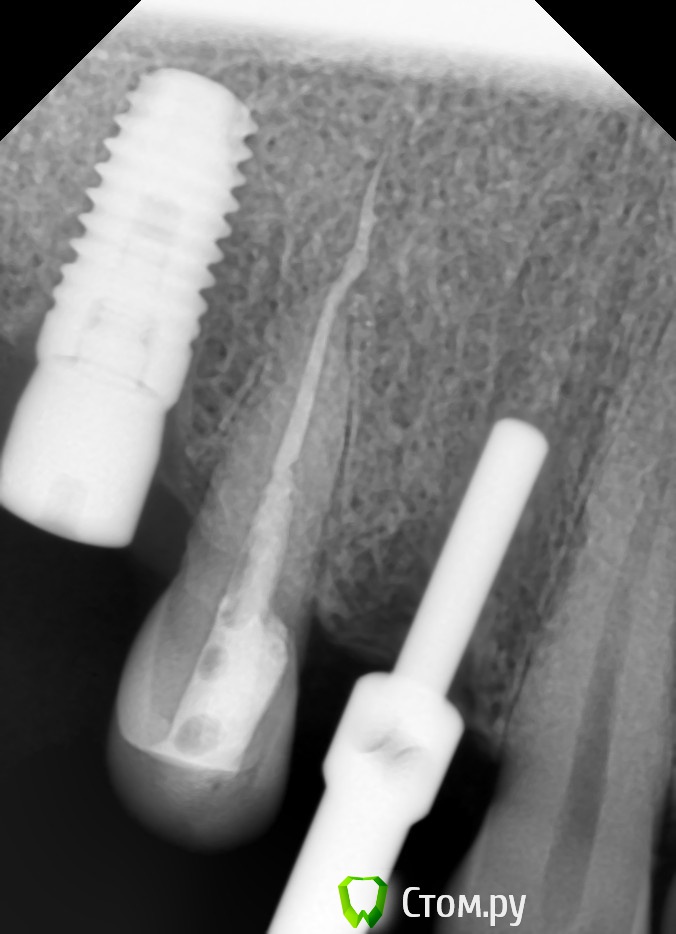

red_butler Опубликовано 23 ноября, 2013 Поделиться Опубликовано 23 ноября, 2013 У нас обязательной частью протокола являются снимки с пинами параллельности, не раз выручали Ссылка на комментарий

pit Опубликовано 23 ноября, 2013 Поделиться Опубликовано 23 ноября, 2013 У нас обязательной частью протокола являются снимки с пинами параллельности, не раз выручалиОПГ или прицельные? Ссылка на комментарий

red_butler Опубликовано 23 ноября, 2013 Поделиться Опубликовано 23 ноября, 2013 ОПГ или прицельные?Чаще прицельные, с пинами ОПГ плохо получается - рот сильно открыт. Выручают нобелевские пины Ссылка на комментарий

Большой Зеленый Опубликовано 23 ноября, 2013 Автор Поделиться Опубликовано 23 ноября, 2013 http://i016.radikal.ru/1504/ae/1eb7db3d9bc5.jpg вроде не критично ) Ссылка на комментарий

pit Опубликовано 23 ноября, 2013 Поделиться Опубликовано 23 ноября, 2013 вроде не критично )Да вообще норм. Но в 3-м секторе дистальный наклон имеется. Ссылка на комментарий

Большой Зеленый Опубликовано 23 ноября, 2013 Автор Поделиться Опубликовано 23 ноября, 2013 Мне помогаютНу вот сделали снимок и видите что немного не туда .Как поменять направление если пилотом уже прошли? Зенковочной фрезой ? Ссылка на комментарий

red_butler Опубликовано 23 ноября, 2013 Поделиться Опубликовано 23 ноября, 2013 Ну вот сделали снимок и видите что немного не туда .Как поменять направление если пилотом уже прошли? Зенковочной фрезой ?На этапе пилота менять направление очень просто, можно изменить угол, или чуть в сторону уйти. Особенно удобно корейскими пилотами. Но это конечно от безысходности. Ссылка на комментарий

pit Опубликовано 23 ноября, 2013 Поделиться Опубликовано 23 ноября, 2013 На этапе пилота менять направление очень просто, можно изменить угол, или чуть в сторону уйти. Особенно удобно корейскими пилотами. Но это конечно от безысходности.Еще лучше трехгранной фрезой 3 Ссылка на комментарий